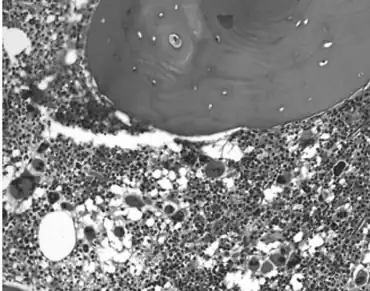

Essential thrombocythemia (ET) is a rare chronic blood cancer (myeloproliferative neoplasm) characterised by the overproduction of platelets (thrombocytes) by megakaryocytes in the bone marrow.[1] It may, albeit rarely, develop into acute myeloid leukemia or myelofibrosis.[1] It is a type of myeloproliferative neoplasm (blood cancers) wherein the body makes too many white or red blood cells, or platelets).[1]

In ET, megakaryocytes are more sensitive to growth factors.[5] Platelets derived from the abnormal megakaryocytes are activated, which, along with the elevated platelet count, contributes to the likelihood of forming blood clots.[6] The increased possibility of bleeding when the platelet count is over 1 million is due to von Willebrand factor (vWF) sequestration by the increased mass of platelets, leaving insufficient vWF for platelet adhesion.[6] A mutation in the JAK2 kinase (V617F) is present in 40–50% of cases and is diagnostic if present.[1][6] JAK2 is a member of the Janus kinase family.[1][6]